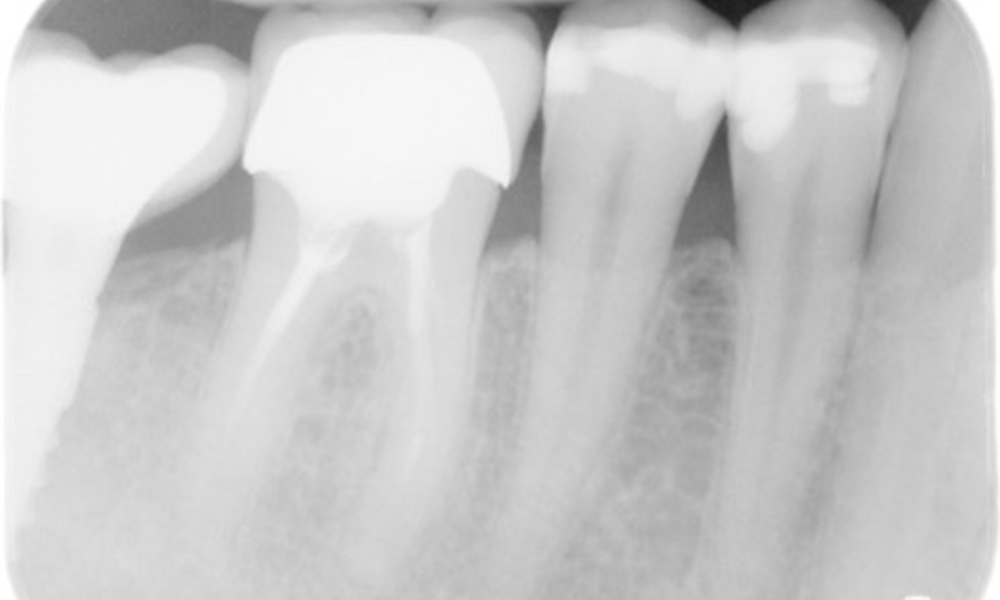

Рентгенова снимка (или рентгенова снимка на захапката)

Рентгенова снимка (или рентгенова снимка на захапката), заснета на: 18/02/2021

Рентгеновата снимка показва загуба на кост